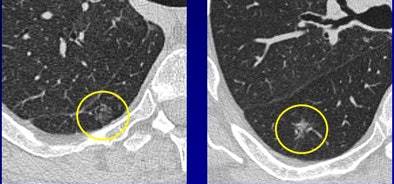

The GGOs that resolved were significantly more often lobular (p = 0.006) and polygonal in shape (p = 0.02) compared to persistent GGOs. Most surprising to the researchers were disappearing nodules that were larger at baseline in both axial diameter (p < 0.0001) and height (p = 0.0002) compared to localized GGOs that did not disappear at follow-up. Finally, the vanishing GGOs were more often of mixed density (p = 0.003) compared to persistent nodules, Ferretti said.

"Malignancy (patterns) are clearly different from other studies," he said. "We showed that mixed GGOs are more often malignant than pure GGOs. We also demonstrated that lobular and polygonal-shaped GGOs are a sign of benignity, as demonstrated by other series.... (Large) size, which is usually a sign of malignancy in other nodules, is also a sign of disappearance in our study -- which indicates we should follow these patients."

Differentiation of flat from nodular morphologies is crucial to the prognostic value of the studies, Ferretti added. At baseline screening and follow-up, sagittal and coronal reconstructions should be performed to distinguish flat GGOs from true nodular lesions.

"Some CT characteristics of resolving GGOs and malignant lesions are the same, which indicate that we should follow these patients with short-term follow-up and histological verification," he said.